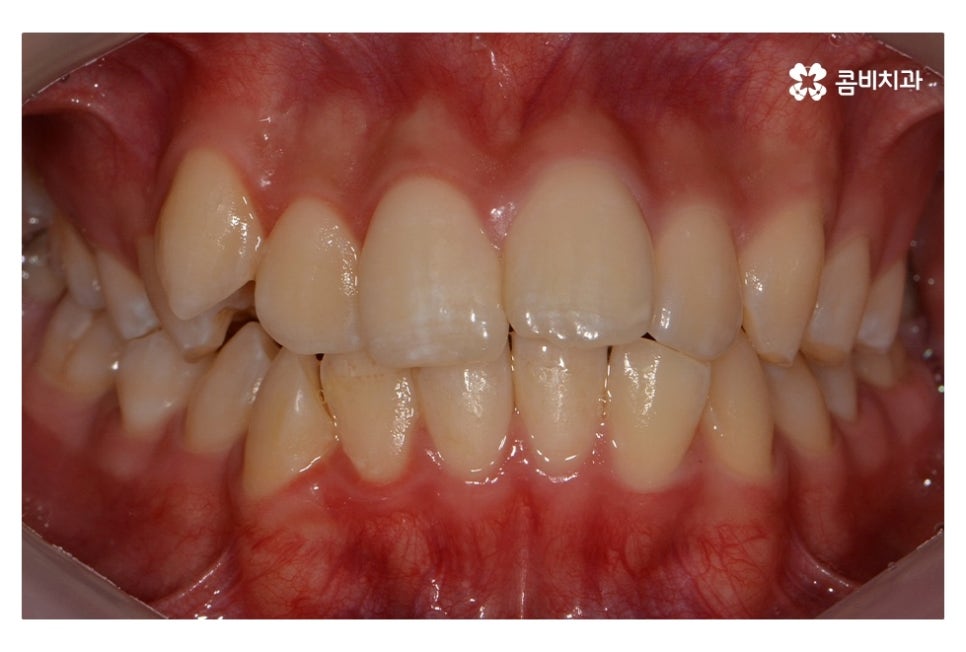

오늘 보여드릴 중학생치아교정 사례의 경우에는

악골의 위치는 정상적인 상태에서 불규칙한 치열로 인해

교정 치료를 진행한 사례라고 할 수 있어요.